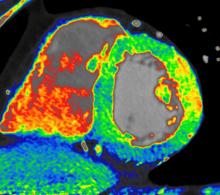

Trends and new technology for cardiac computed tomography angiography (CCTA) were highlighted during the 2012 Society of Cardiovascular CT (SCCT) annual scientific meeting in July in Baltimore, Md. Major topics included the development of fractional flow reserve (FFR)-CT imaging, perfusion imaging, imaging for transcatheter aortic valve replacement (TAVR) and analysis software advancements.